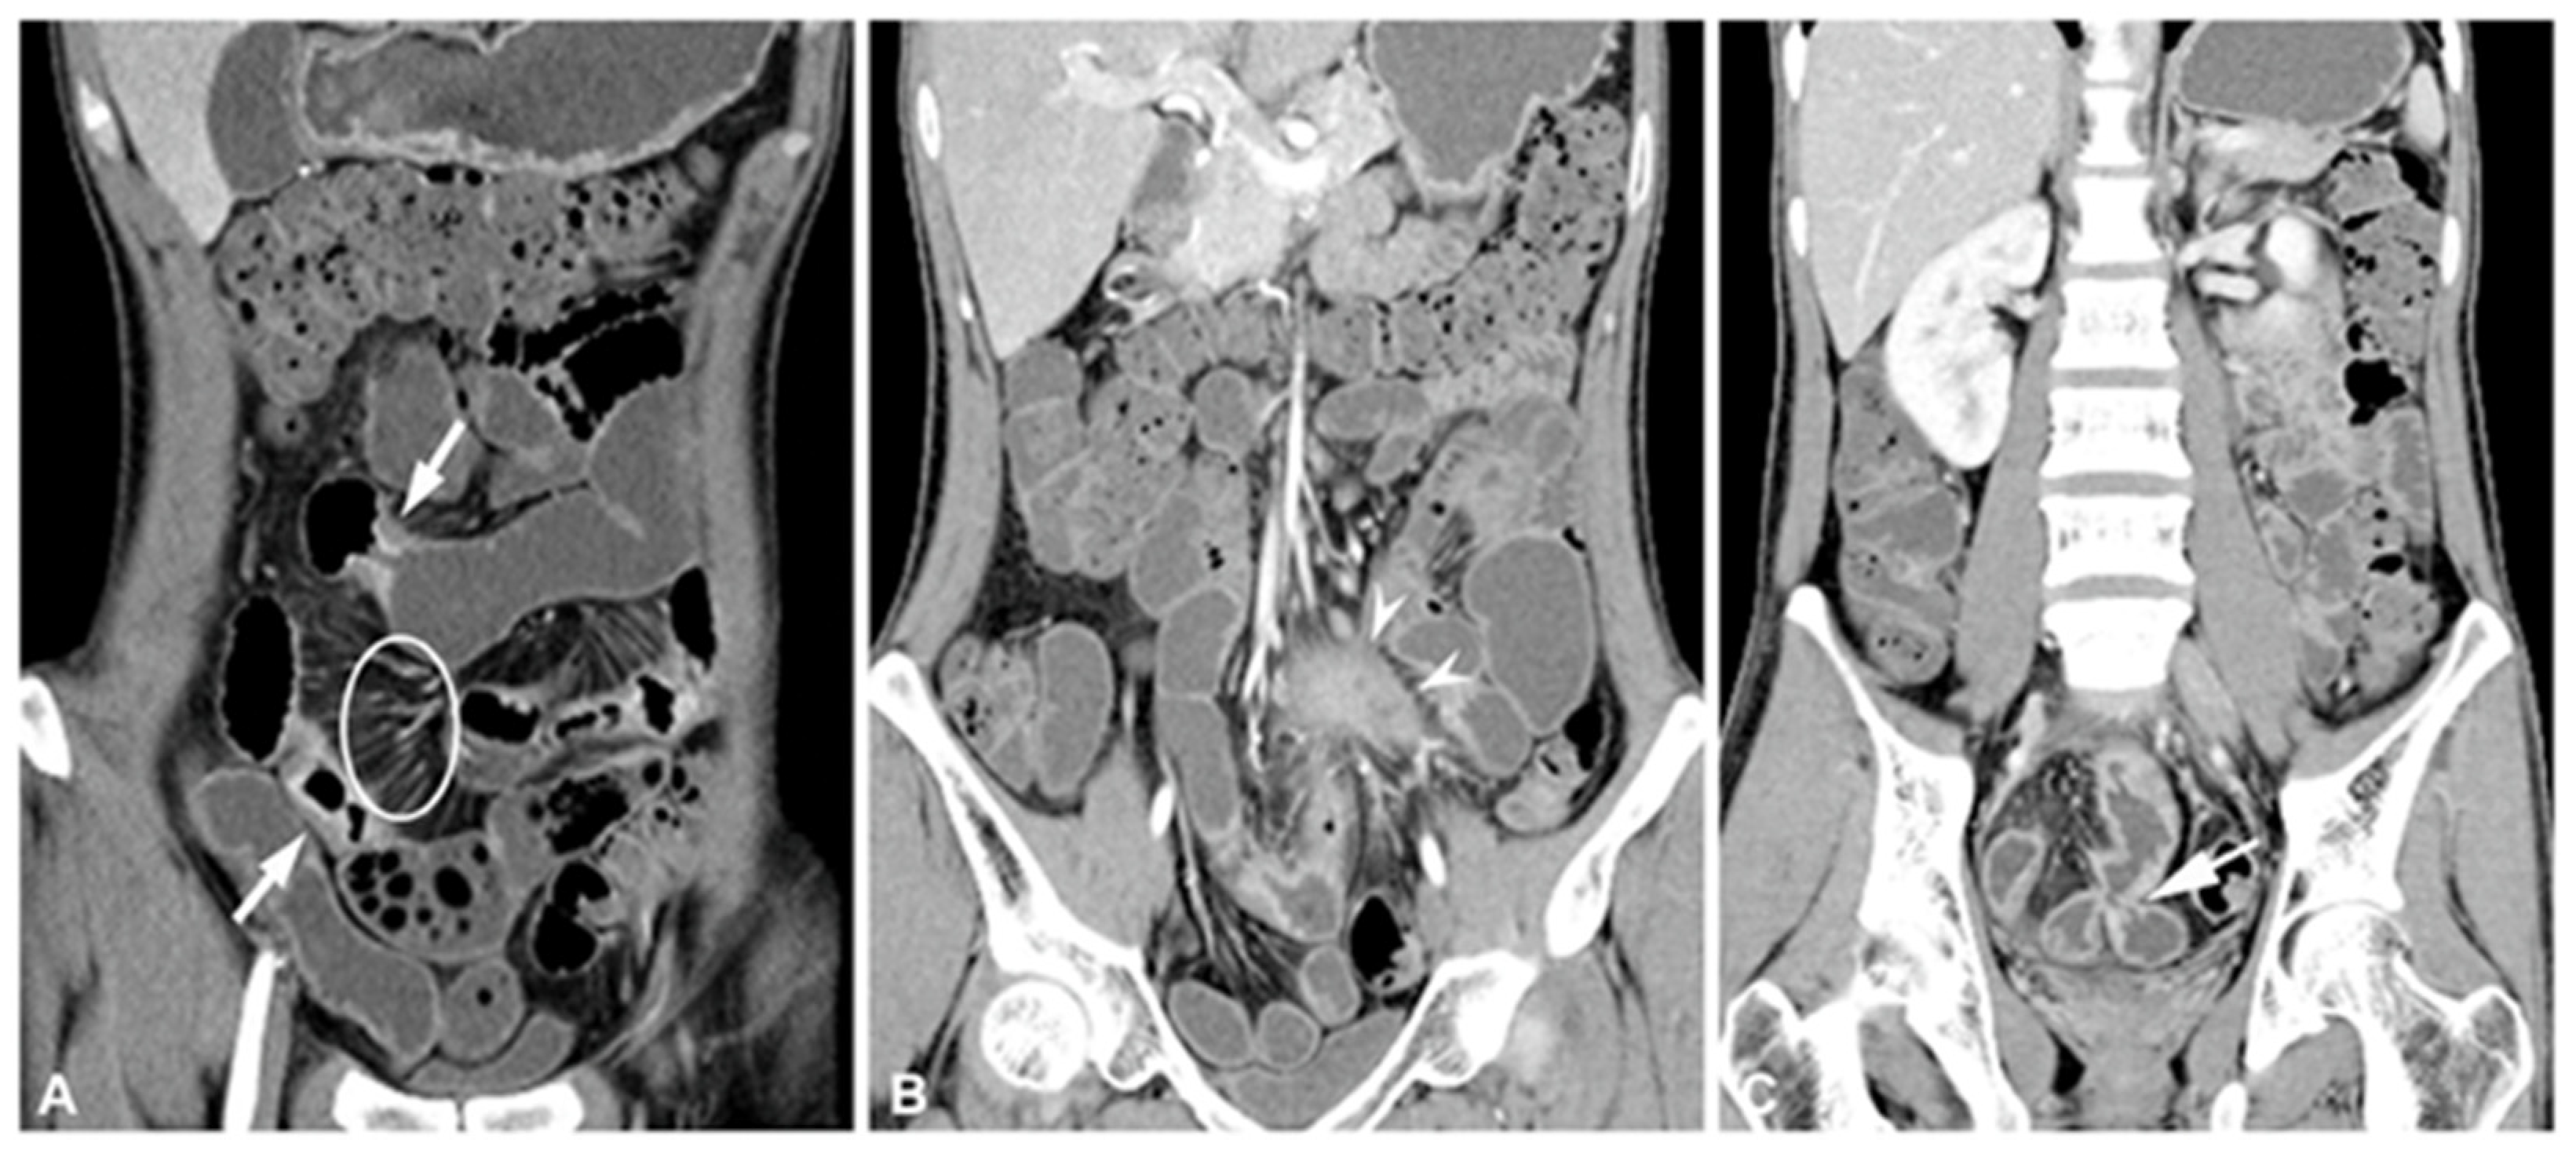

- Minordi, L.M.; Bevere, A.; Papa, A.; Larosa, L.; Manfredi, R. CT and MRI Evaluations in Crohn’s Complications: A Guide for the Radiologist. Acad. Radiol. 2022, 29, 1206–1227. [Google Scholar] [CrossRef]

- Bartlett, D.J.; Ramos, G.P.; Fletcher, J.G.; Bruining, D.H. Imaging Evaluation of Inflammatory Bowel Disease Complications. Gastrointest. Endosc. Clin. N. Am. 2022, 32, 651–673. [Google Scholar] [CrossRef] [PubMed]